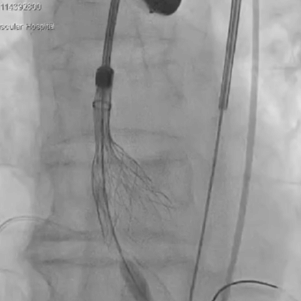

为期两天的手术联播过程中,来自厦门大学心血管病医院王斌教授,首都医科大学附属北京安贞医院宋光远教授,阜外华中心血管病医院王圣教授,南京医科大学第一附属医院孙伟教授,广东省人民医院李捷教授,中国医学科学院阜外医院吴永健教授,中南大学湘雅二医院方臻飞教授,浙江大学医学院附属第二医院王建安教授,北京大学第三医院唐熠达教授分别带来了精彩的TAVR实战案例。

从三叶瓣重度钙化到二叶瓣畸形的根部解剖,从单纯主动脉瓣反流到入路极端迂曲挑战的案例。TaurusOne凭借其优异的柔顺性,支撑力强及内外层双侧裙边的特点,都能从容应对复杂的临床患者解剖结构。从患者的临床选择到术后的长久获益,从手术入路的种类到术中操作的注意事项,从围术期卒中的循证医学到术后的抗凝抗栓用药规范,在线专家共同交流彼此中心的围术期TAVR经验和分享现阶段经导管主动脉瓣置换的诊疗策略。针对当前TAVR领域多个热点学术问题进行了热烈的讨论,现场可谓精彩纷呈、高潮迭起。专家们纷纷借此契机相互交流探讨,分享各自的单中心经验,力求进一步提升TAVR手术的安全性和有效性,为主动脉瓣相关疾病的患者带来长远综合获益。